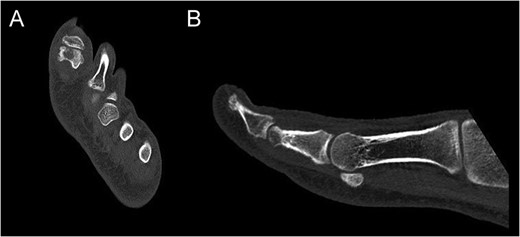

Preoperative CT of the proximal phalanx of the left hallux: axial (A), and sagittal view (B), showing the osteolytic nidus of the tumor with central calcification surrounded by a slight sclerotic halo: the standard image of OO.